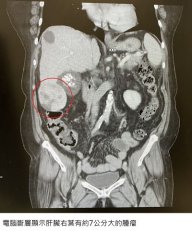

平時沒症狀卻罹患C肝肝癌! 健檢救命揪”肝”心 TNN |

一名69歲陳姓婦人,日前體檢抽血報告顯示C肝病毒量和肝癌指數都偏高,超音波檢查時發現肝臟右葉有約7公分大的腫瘤,至長安醫院肝膽腸胃科就診,進一步安排電腦斷層確診為肝細胞癌。所幸癌細胞並未擴散,...(詳全文) |